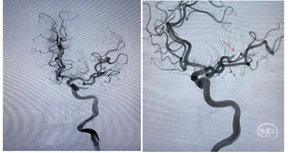

右侧颈总造影发现,右侧颈内动脉起始处有斑块,两处充盈缺损。

使用泥鳅导丝试探,很幸运,毫不费劲就通过了狭窄处,因此考虑此处未完全闭塞,而且远处的栓子可能就来源于此处。将5F125cm Navien沿着泥鳅导丝轻松通过狭窄处,进行抽吸清理颈内动脉可能滞留血栓。跟进8F导引导管通过狭窄部位起到支撑作用。

上干和大脑前为功能区血管,应该开通:

先开通大脑中M2段。支架导管到位,确认远端通畅,尼科医疗的Reco支架3X20mm到位,5F Navien跟到M1,一边抽吸一边拉栓,一把拉通。

注意:应该微导管半收拢支架钳夹血栓,缓慢回拉,防止牵拉血管支撑组织导致脑出血。

再开通大脑前A2段,同样尼科医疗的Reco支架3X20mm到位,5F Navien 跟进A1,半收拢支架,一边抽吸一边拉栓,一把拉通。

回头处理颈内动脉起始部。常规保护伞4-6mm保护下行4-6mm球囊扩张,并自膨支架7-9-40mm植入。